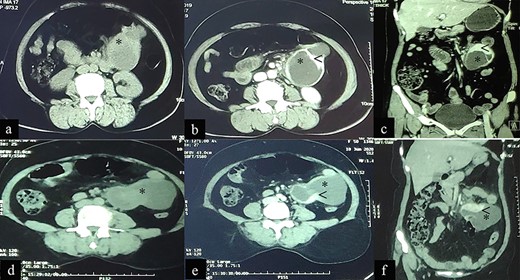

A 62-year-old female agricultural worker, presented with complaints of gradual abdominal distension over the past 2 years, associated with mild to moderate abdominal pain (exacerbated by meals), anorexia and gradual weight loss (~15-kg weight loss in 2 years). She was first seen at another hospital 18-month ago where contrast enhanced computed tomography (CECT) of abdomen revealed two heterogeneously enhancing exophytic lesions; one in the second part of the duodenum (43 mm × 36 mm) and the second in the right lumbar region (50 mm × 34 mm). The radiologic interpretation suggested EGIST (Fig. 1a–c), but the patient elected to not undergo any further workup or treatment.

Case 1: CT imaging of extragastrointestinal stromal tumor. (a) Non-contrast axial, (b, c) contrast enhanced axial and coronal reformatted CT images of abdomen demonstrate heterogeneously enhancing confluent mass (*) in peritoneal cavity anterior to the iliac vessels with central area of necrosis (<) peripherally displacing mesenteric vessels (arrow) and bowel. (d–f) Non-contrast axial, contrast enhanced axial and coronal reformatted CT images of abdomen of same patient after 1-year follow-up showing increased interval size of the lesion (*).

The patient presented to our outpatient clinic because of gradually worsening symptoms. She was alert and oriented with no acute distress and normal vital signs. With the exception of her abdominal examination, no abnormalities were detected. Her abdominal examination was remarkable for abdomen distension with burn scars on the anterior abdominal wall in the epigastric and left hypogastric region. There were no striae, dilated veins, rashes or visible peristalsis and bowel sounds were normal. The abdomen was soft with a large, firm and fixed mass (~15 cm × 15 cm) palpated in the epigastric/left hypochondriac region. Rectal examination was unremarkable. Laboratory studies included a complete blood count, renal function test, liver function test and a coagulation profile. All were normal. A repeat CECT of abdomen and pelvis showed: a large heterogeneously enhancing exophytic lesion (size ~18 cm) abutting the pancreatic head and superior mesenteric vessels, features suggestive of an EGIST (Fig. 1d–f).